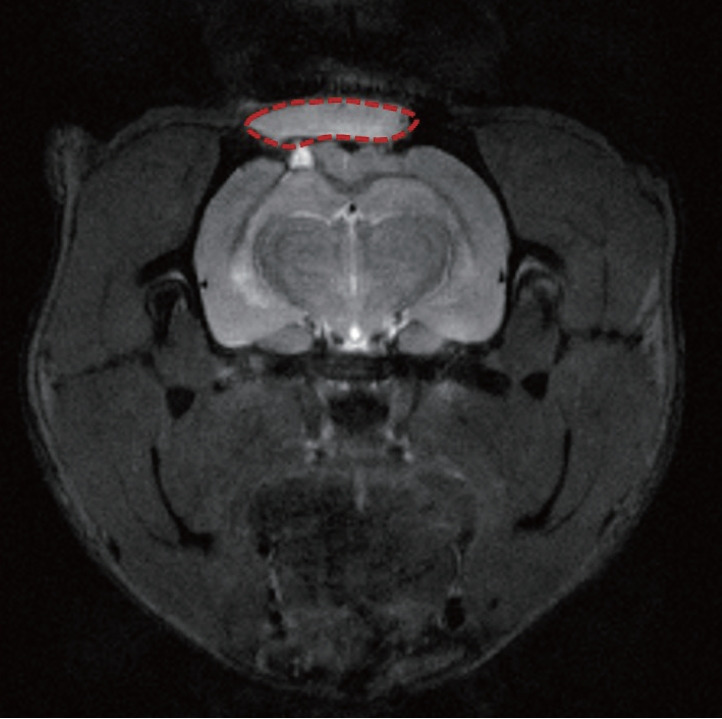

Methods: HA photosealants were applied to the incised dura in a rat craniectomy and durotomy. The HA photosealant quickly sealed the wound upon low-energy visible light exposure (405 nm, <5 seconds, < 1 J/cm2). The degradation of HA photosealants was tracked through serial MRI scans at 1, 2, and 4 weeks post-application. The remaining area of HA photosealants on the dura was measured using image processing program for volumetric analysis. Additionally, histopathological analyses were performed to evaluate the biocompatibility and effectiveness of the dural repair.

Results: The MRI and histopathological analyses showed that the HA photosealant achieved progressive degradation while successfully preventing CSF leakage without any adverse tissue reactions. The residual area of HA photosealants measured at 2 weeks ranged from 41.35% to 94.88%, with an average of 66.57%. At 4 weeks, a more distinct degradation pattern was observed compared to 2 weeks, showing a residual area of 10.28% to 56.11%. The HA photosealant maintained structural integrity until dural regeneration was completed.